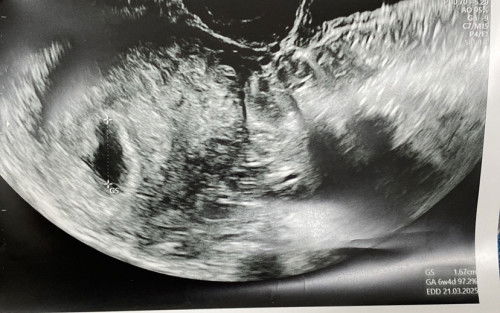

Scan TVS at week 5

Hi mommies, doctor kira saya dah 5w3d tapi dekat scanner 6w4d. which one nak ikut eh? and normal ke kantung kosong macam ni and size 1.67cm? any experienced mommies boleh jawab 🙏🏻. #firsttimemom

for now follow 5w3d. nanti masa buka buku 12w dktr akn scan lagi sekali utk confirm edd. kantung kosong is normal..dlm 7-8w baru nmpk janin...depends.

Normal sis sy pun scan 6w nmpk kantung je sy terlupa pregnant 1st aritu 7w br nmpk. So nati awk repeat scan lg 2w or 3w